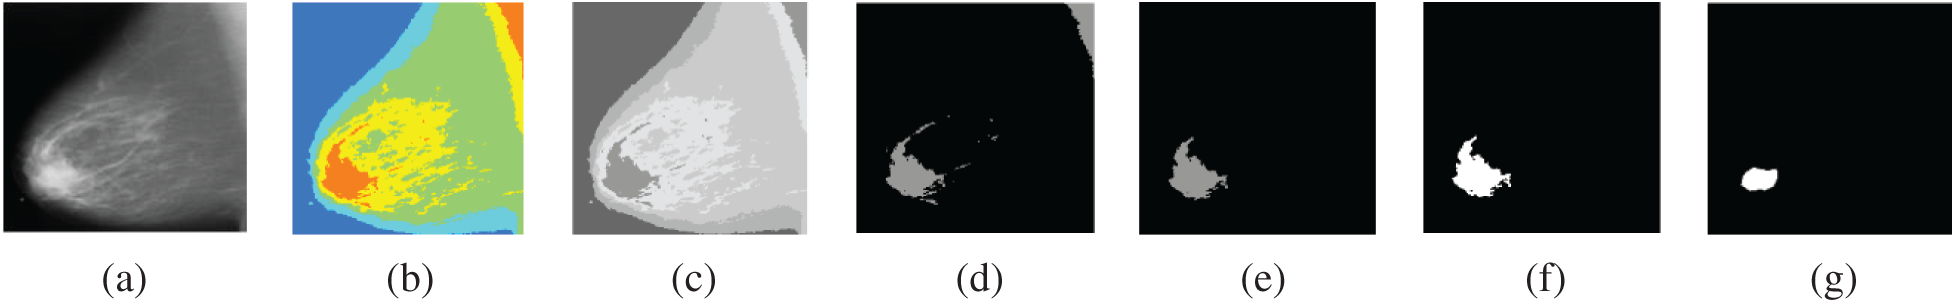

Finally, the third experiment is performed to evaluate the proposed segmentation algorithm of breast cancer lesions. The results on MLO and CC images are shown in Figs. 13 and 14, respectively.

Figure 13: Segmentation of breast cancer lesions in an MLO image (a) Original image (b) RGB image (c) Gray-scale image (d) Segmented image (e) ROI image (f) Tumor image (g) Reference image